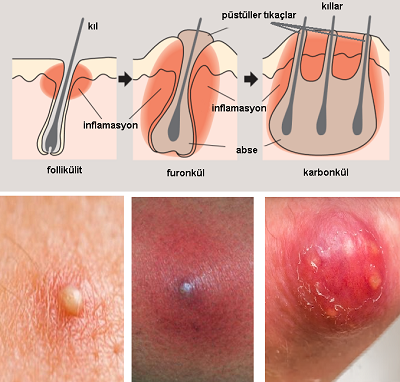

2. BAKTERİYEL DERİ HASTALIKLARI